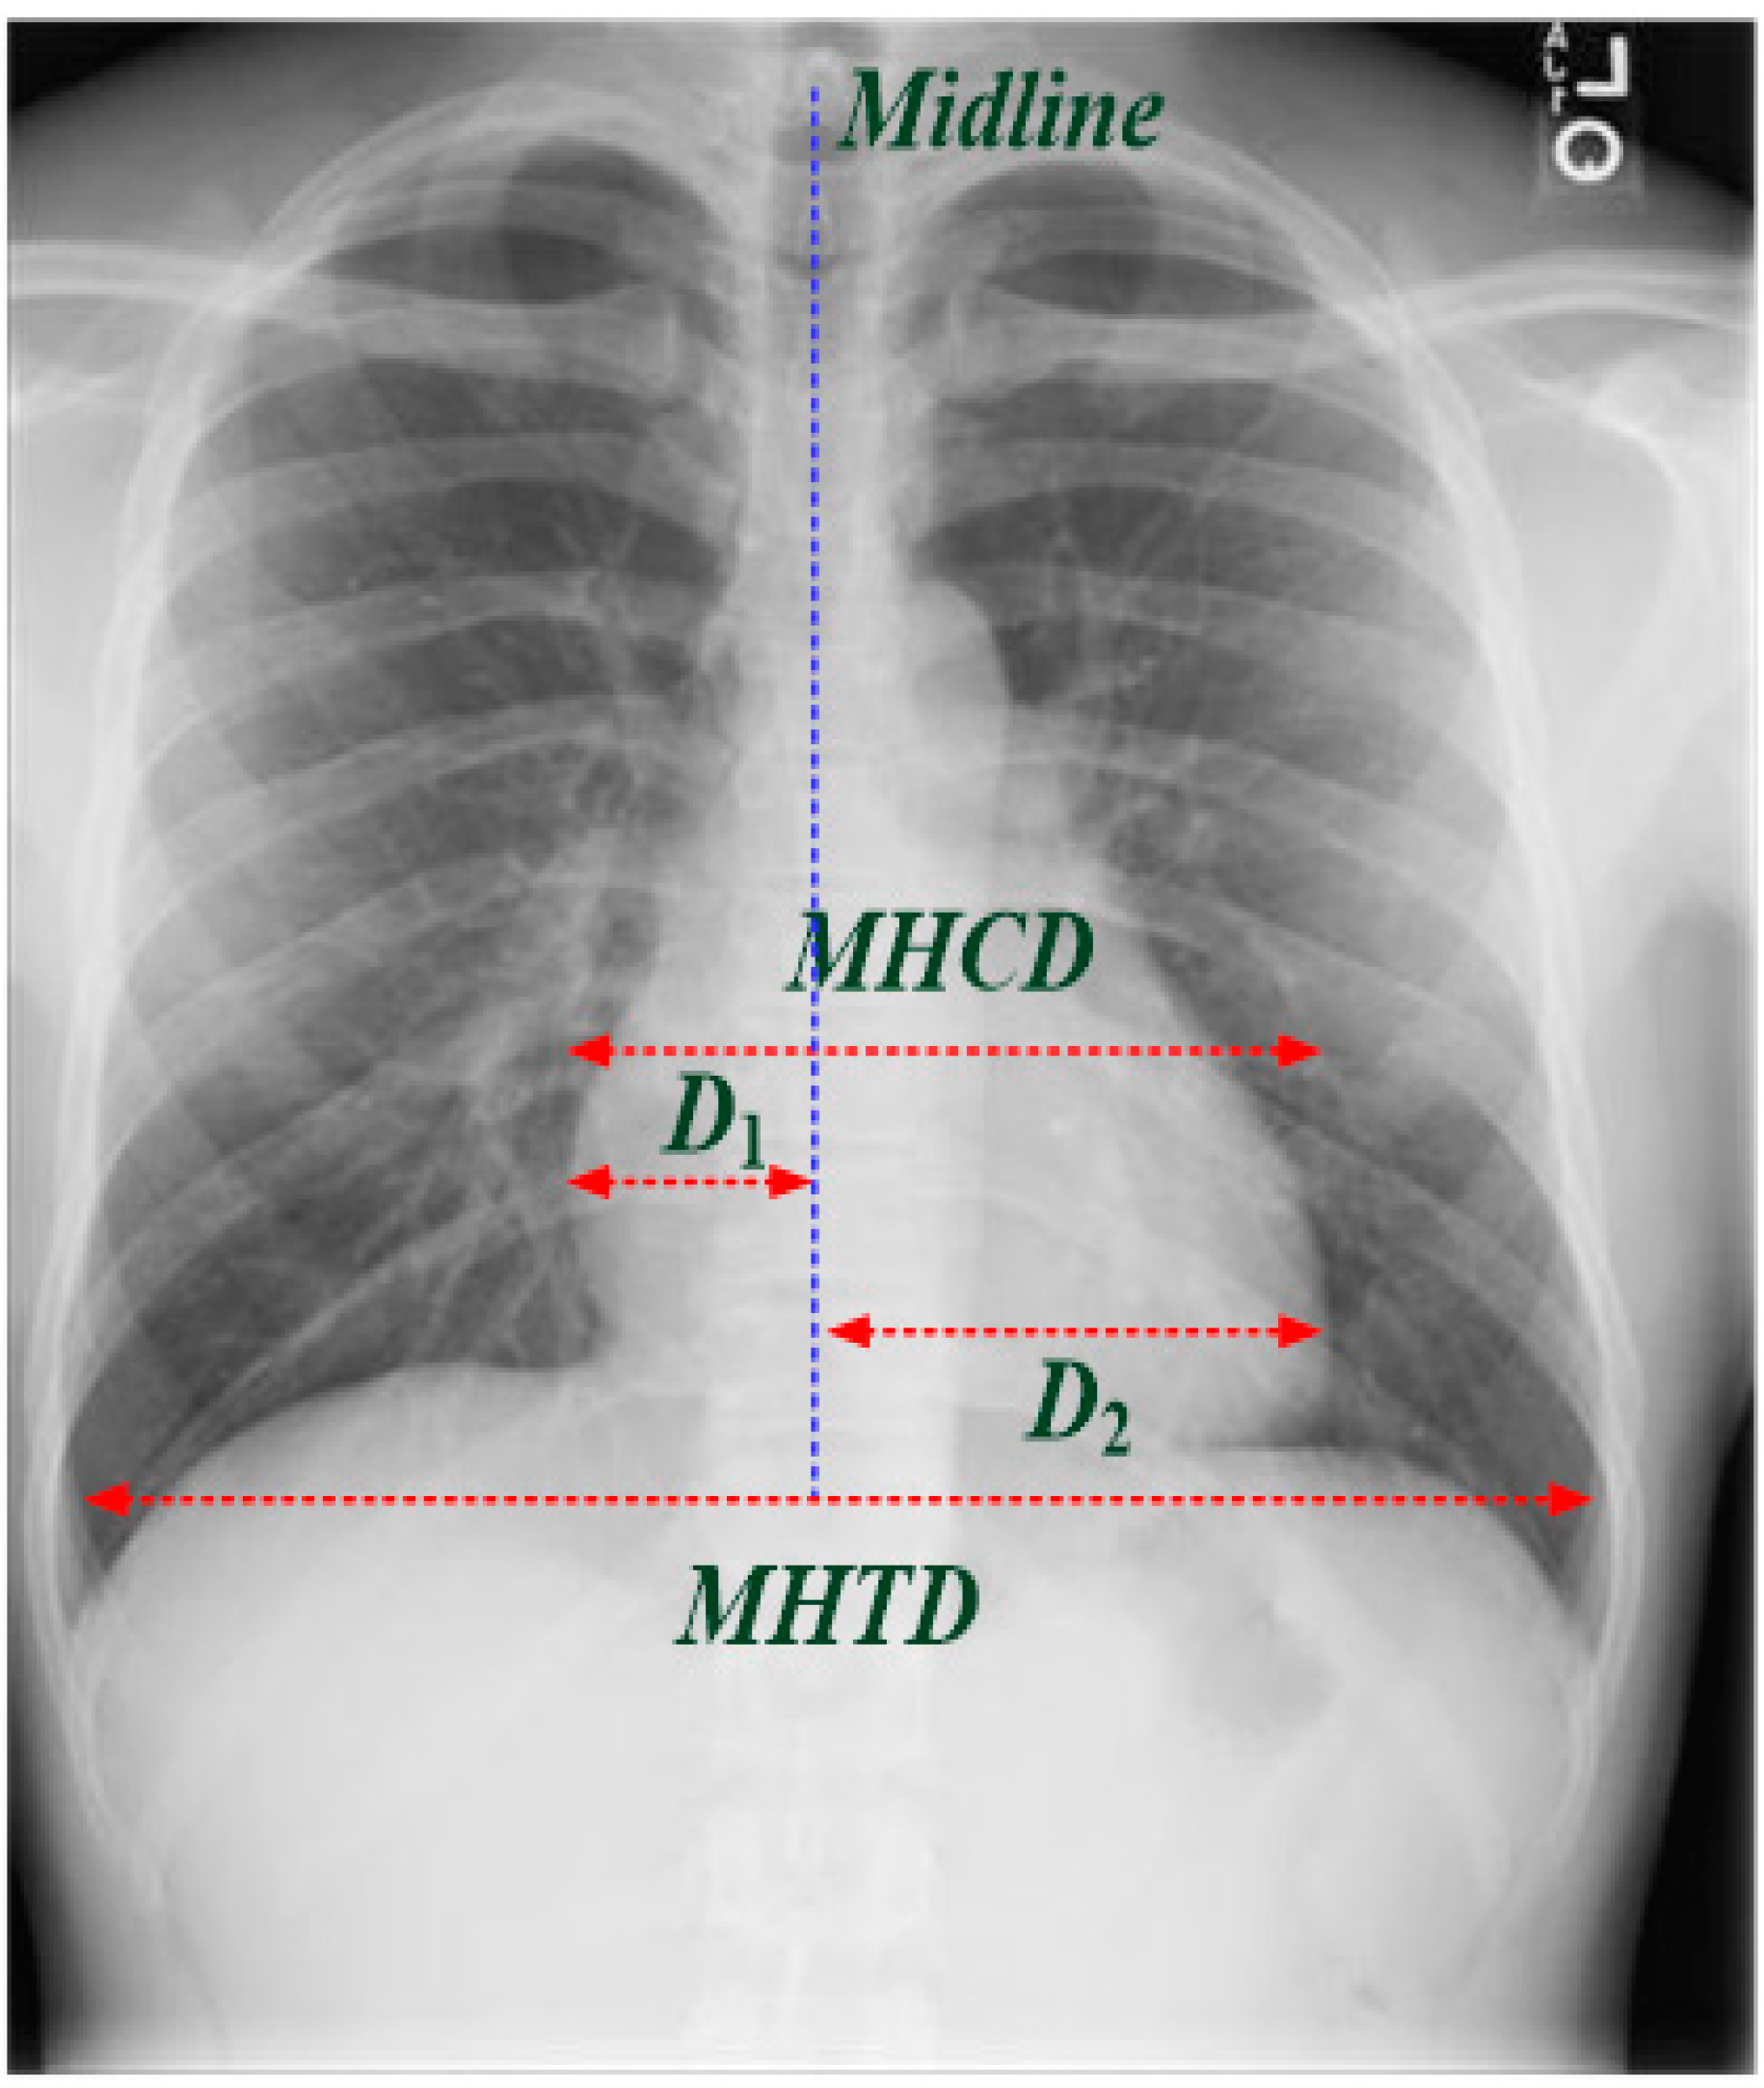

- Li, Z.; Hou, Z.; Chen, C.; Hao, Z.; An, Y.; Liang, S.; Lu, B. Automatic Cardiothoracic Ratio Calculation with Deep Learning. IEEE Access 2019, 7, 37749–37756. [Google Scholar] [CrossRef]

- Truszkiewicz, K.; Poręba, R.; Gać, P. Radiological Cardiothoracic Ratio in Evidence-Based Medicine. J. Clin. Med. 2021, 10, 2016. [Google Scholar] [CrossRef] [PubMed]